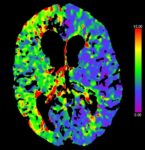

Porážka. Mŕtvica. Mozgový infarkt. Iktus. Toto všetko sú rôzne označenia pre rovnakú diagnózu. Ľudovo sa jej hovorí najčastejšie porážka. Vyplýva to pravdepodobne z najčastejšieho osudu chorých… mŕtvica zmenila človeka natoľko, že už nikdy nebol ako predtým, mal zjavné poruchy pohybu, reči, citlivosti. Nezriedka sa stalo, že pacient po mŕtvici do niekoľkých minút či hodín zomrel. Príčinou mozgovej príhody je náhle či... - Tranzientný ischemický atak – TIA